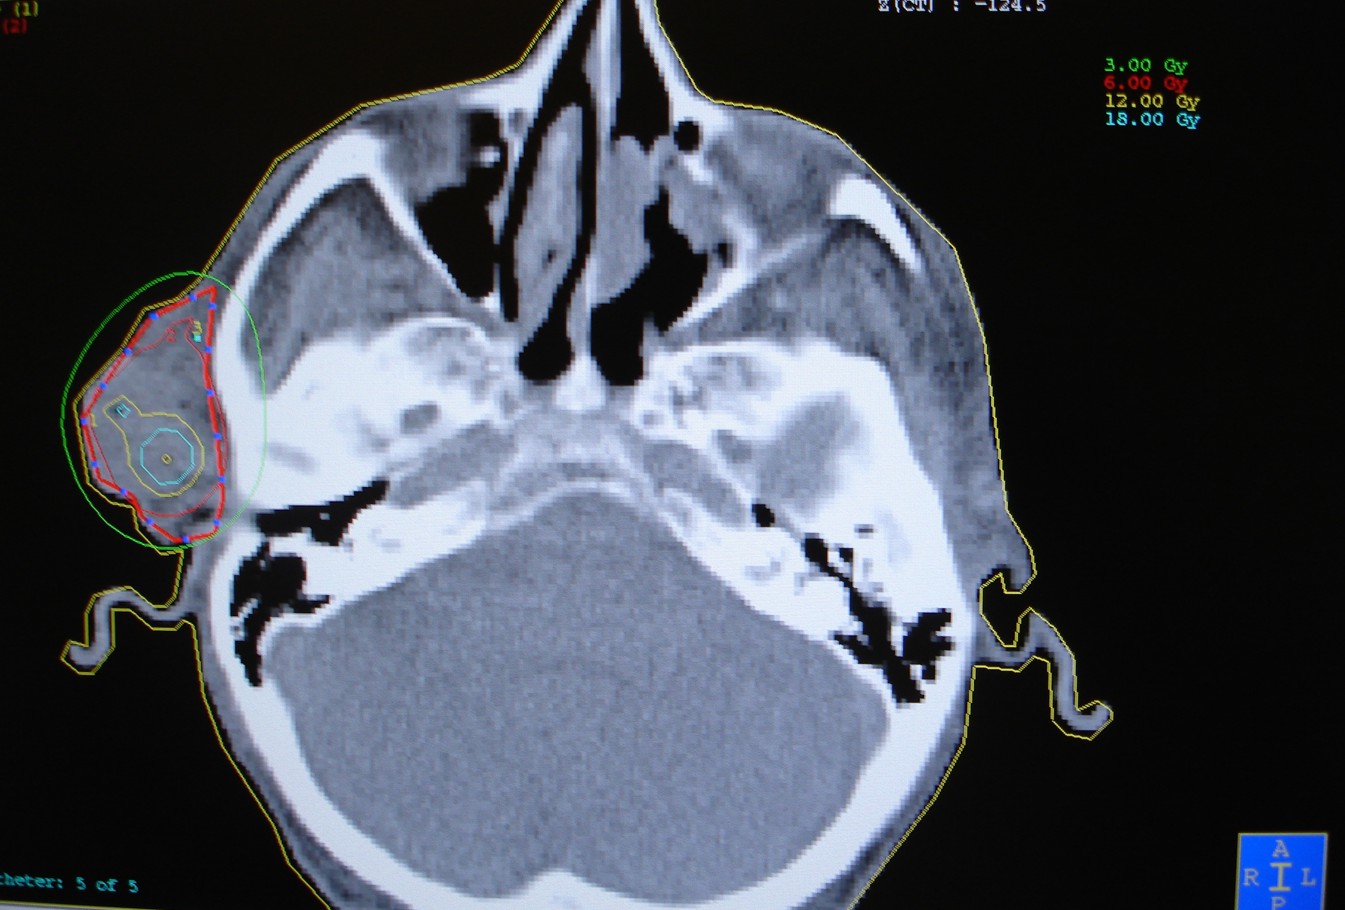

Zaawansowany rak skóry twarzy okolicy przedusznej. Zastosowano brachyterapię HDR, podano 10 frakcji po 5 Gy, raz dziennie. W znieczuleniu miejscowym założono 5 aplikatorów śródtkankowych elastycznych.

Planowanie leczenia - skan TK, wrysowany CTV (Clinical Target Volume), widok izodoz